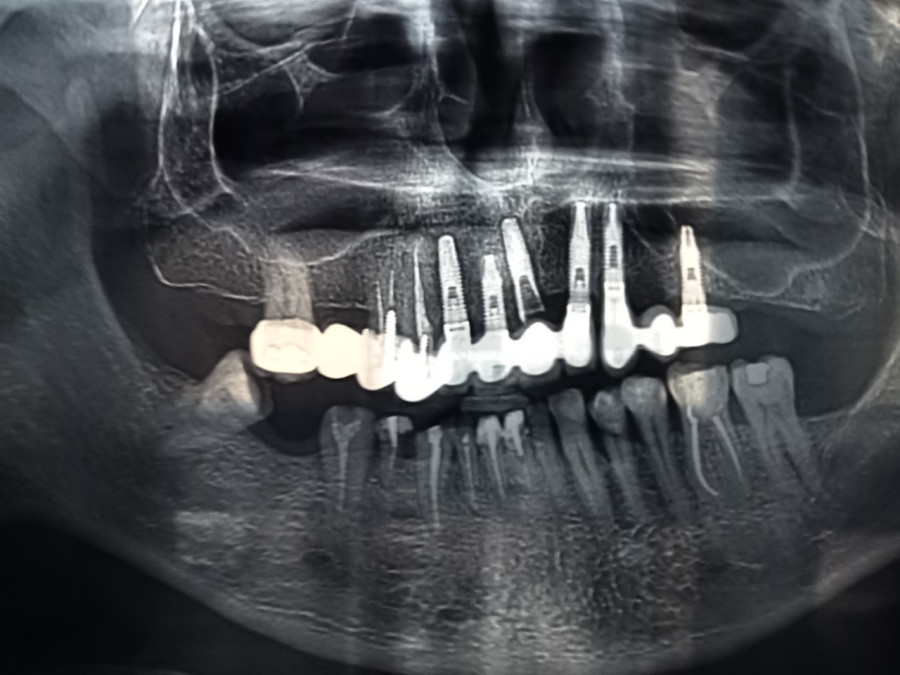

Metacuerpo / Mandíbulas y maseteros/ ay, ay, son su yo verdadero/ lo demás es sólo relleno

Y el titanio no es ya sólo química/ ni la revolución es ya un objetivo titánico/ porque los maseteros se vuelven titánicos/ porque la conciencia así lo exige

Érase un hombre titánico/ porque mordía la vida/ y después la saboreaba/ porque masticaba la vida/ y después la saboreaba/ y sus maseteros/ rompían un tornillo de titanio

A la luz de la luna llena/ los maseteros, ay, rompían/ un tornillo de titanio/ y las mandíbulas se quedaban/ ay, los restos del tornillo/ a la luz de la luna llena/ ay, las hienas, las hienas

Delicada y suavemente/ sigilosa, sinuosamente/ ¡ay!, se desliza el duende/ entre los muy aterradores/ maseteros trituradores/ ¡ay!, se desliza el duende/ entre crecientes/ huesos crujientes/ ¡ay!, se desliza el duende/ entre el quebrado tornillo/ de fatigado titanio/ ¡ay!, se desliza el duende/ delicada y suavemente/ sigilosa, sinuosamente